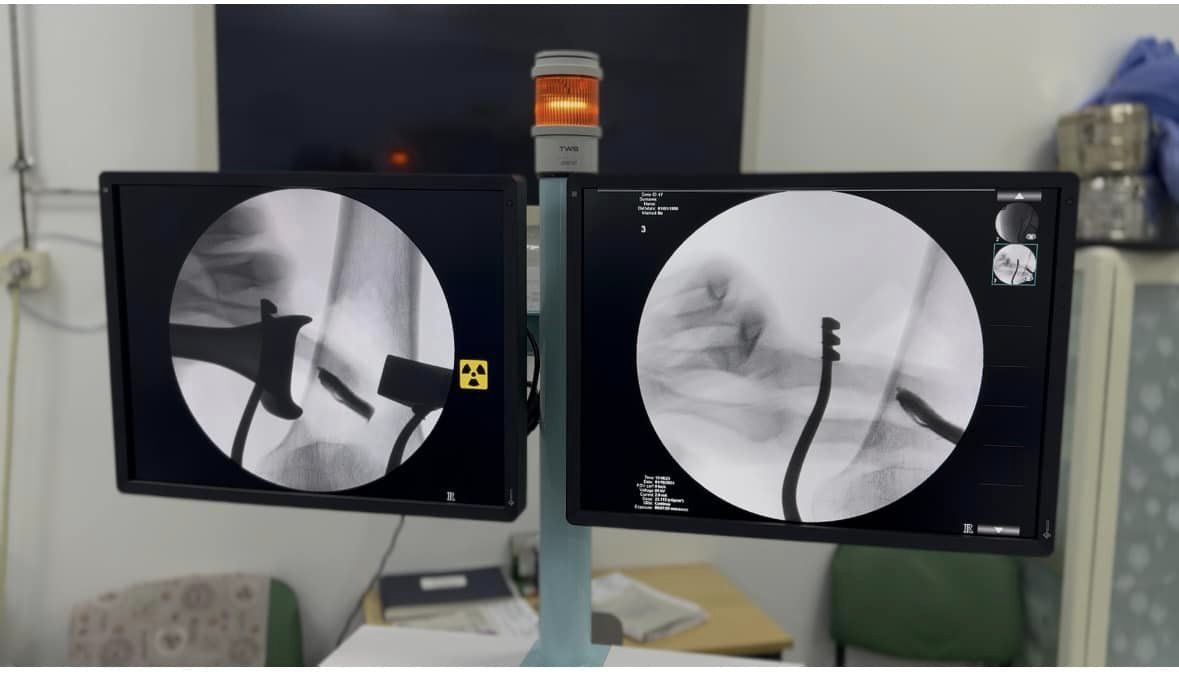

До лікарні у Дніпрі потрапила жінка, яка постраждала від ракетного удару. Уламок, який стояв між кісткою і магістральною артерією, міг спровокувати кровотечу та викликав нестерпний біль.

Хірурги провели операцію з використанням новітньої апаратури та видалили уламок.